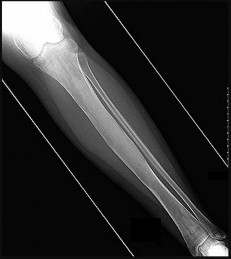

Figures 9a through 9d are the anteroposterior and lateral radiographs, CT scan, and technetium bone scan of a 12-year-old boy who has experienced 7 months of pain in his lower leg. The pain limits his ability to participate in sports and he is having difficulty sleeping. He is afebrile, and laboratory study findings including an erythrocyte sedimentation rate, C-reactive protein, and complete blood count are within normal limits.

The images and clinical history support a diagnosis of osteoid osteoma, which most commonly occurs in adolescence. Although these lesions can be seen in any bone, they are usually located in the femur and tibia. The significant inflammatory response to this tumor is secondary to high levels of prostaglandin production. Characteristic night pain is relieved with nonsteroidal anti-inflammatory drugs (NSAIDs) or by aspirin.

Radiographic images show thickened bone and a small central nidus. Thin-cut CT scan is the imaging of choice to visualize the nidus. A bone scan is associated with uptake but is not specific. Treatment options include expectant management with NSAIDs and observation under the premise that these lesions eventually burn out. Contemporary treatment involves RFA. Historically, these lesions were treated with en bloc resection; however, this technique has largely fallen out of favor because of the high efficacy and comparative low morbidity associated with RFA.

When an osteoid osteoma occurs in the spine, it is located in the posterior elements, and paraspinal pain and scoliosis often are present.